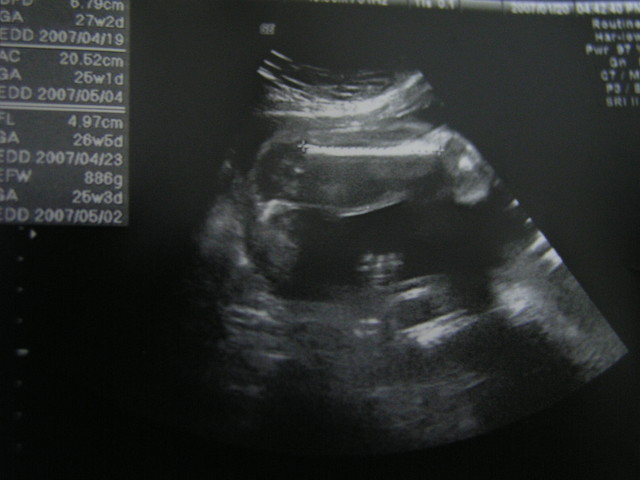

第6次產檢記錄

96/2/10

週數:28週5天

mama體重62KG

抽血:驗B型肝炎

心跳Ump-HR:138bpm

頭圍BPD:7.81cm

肚圍AC:23.91CM

大腿骨FL:5.56CM

體重EFW:1333g

醫生說寶寶長頭髮了

因為我的頭髮不多一度擔心寶寶也會跟我一樣

不過醫師說小寶寶的頭髮應該會很濃密才是(希望囉!)

今天小蘇菲剛好趴著

沒辦法看到她的小臉蛋